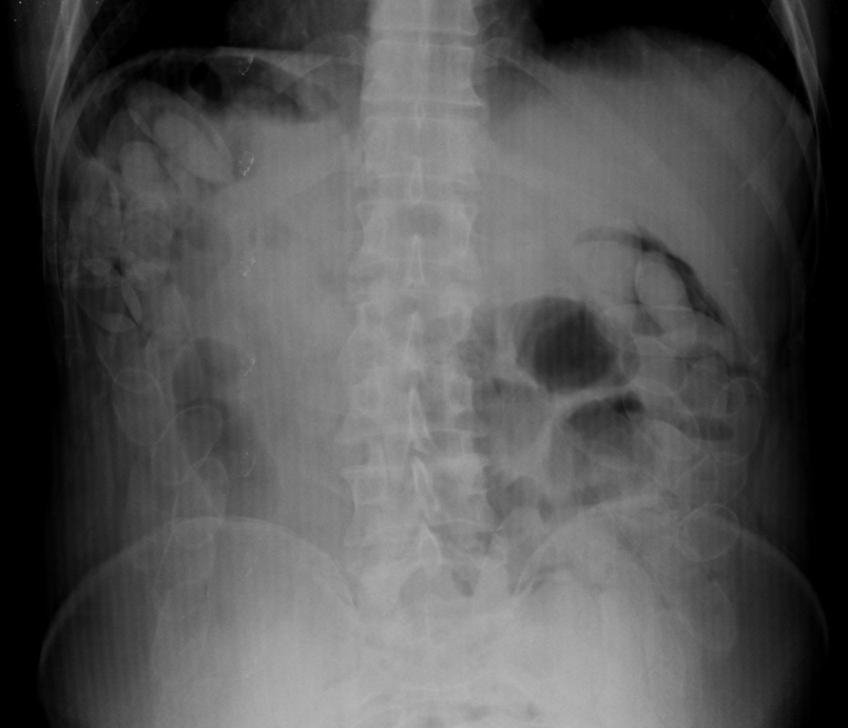

Ante ese hallazgo, la Fiscalía Federal de Salta dispuso que se realice una placa radiográfica sobre el involucrado de nacionalidad boliviana ante la posibilidad de haya ingerido envoltorios con la misma sustancia.

Se trasladó al ciudadano al Hospital de la ciudad de Rosario de la Frontera, en donde se confirmó las sospechas de los gendarmes, quienes hallaron mediante radiografía abdominal que el hombre poseía 92 cápsulas en su estómago, lo que significa un gran riesgo de vida.